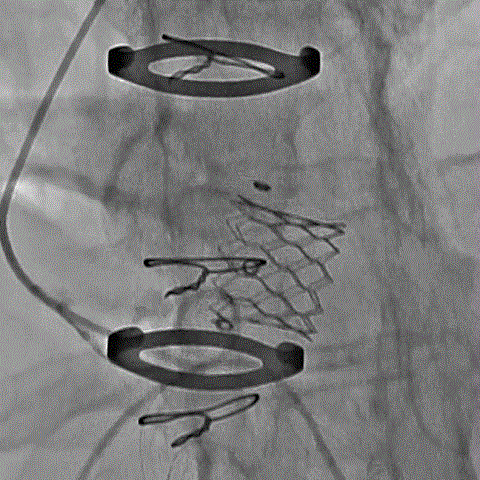

术前经详尽影像学重建和评估,该款人工生物瓣显影不理想,通过CT重建测量瓣环直径,评估冠脉梗阻风险。考虑到患者横位心,主动脉迂曲严重,最终选用经心尖入路,植入21# Renato球扩式瓣中瓣。手术顺利,瓣中瓣植入位置理想,功能表现出色,主动脉瓣峰值流速由术前3.4m/s下降至2.0m/s,平均跨瓣压差由术前32mmHg下降至8mmHg。经食道超声观察无瓣周漏及瓣中反流。

术前经详尽评估患者病情,通过CT重建测量瓣环直径、左室流出道面积。考虑到之前经房间隔入路外科换瓣,房间隔瘢痕严重,最终采用经心尖途径植入25# Renato球扩式瓣中瓣。手术顺利,瓣中瓣植入位置理想,功能表现出色,二尖瓣峰值流速由术前2m/s下降至1.4m/s,平均跨瓣压差由术前10mmHg下降至2mmHg,左室流出道压差正常,经食道超声观察无明显瓣中及瓣周返流。

术前经详尽影像学重建和评估,CT重建测量瓣环直径,评估冠脉梗阻风险及外周血管条件。最终采用经股动脉入路植入21# Renato球扩式瓣中瓣。手术顺利,瓣中瓣植入位置理想,功能表现出色,主动脉瓣峰值流速由术前4m/s下降至2m/s,平均跨瓣压差由术前40mmHg下降至6mmHg。经食道超声观察无瓣周漏及瓣中反流。